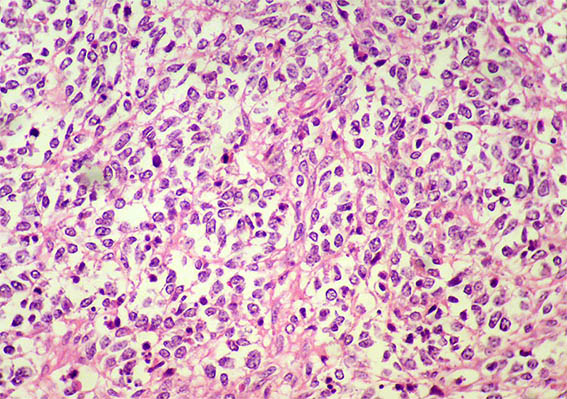

Figure 5. H&E, X400.

Figure 6. H&E, X400.